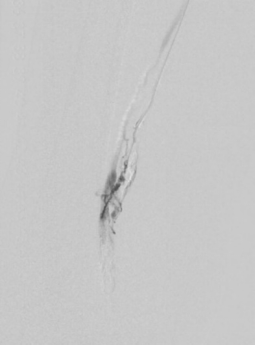

1. 术前造影:

2. 经鞘置入椎管、CXI、V18导丝正向开通股浅动脉下段,导丝通过,导管无法跟进,经皮穿刺钙化灶,导管跟进造影发现位于内膜下。